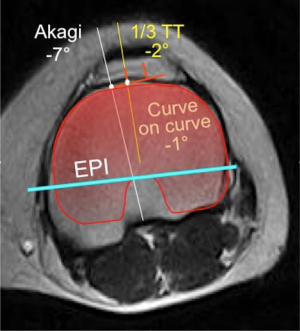

After selecting a single best axial scan, the femoral surgical transepicondylar axis (sTEA), the femoral posterior condylar axis (PCA) and the projection of the medial third of the tibial tubercle on the anterior tibial cortex were identified. For each knee, the sTEA, the PCA and the medial third of the tibial tubercle were projected on a tibial axial cut. The geometric center of the tibial area was also identified. A line was first drawn from the center of the tibial plate to the medial third of the tubercle and then the perpendicular line to the TEA passing through the tibial plate center was identified. At this point, the Akagi’s line was drawn. This landmark was made by a line starting at the medial third of the tibial tubercle and ending at the center of the posterior cruciate ligament tibial insertion. The most appropriate tibial baseplate tracing (size 3 to 8) for the Nex-Gen Total Knee System (Zimmer, Warsaw, USA) was superimposed at this time, matching the anterior tibial cortex with its anterior surface (“Curve-on-Curve Technique”). The rotation of the tibial plate tracing was calculated with respect to the sTEA, the medial third of the tibial tubercle line, the Akagi’s line and the PCA (Figure 1).

The three observers showed an agreement on the localization of the Akagi’s line in 64% of the cases within 3° and in 85% of the cases within 5° (minimum, −16°; maximum, −7°). The average intraclass correlation coefficient was 0.923 (PFI vs. PCM: 0.910; PFI vs. AB: 0.933; PCM vs. AB; 0.927). The observers agreed on the statistically significant evidence that the use of this surgical landmark might lead to internal rotation of the tibial component.

Anterior tibial surface curvature

The three observers showed an agreement on the localization of the anterior tibial surface contour in 89% of the cases within 3° and in 99% of the cases within 5° (minimum, −1°, maximum, +4°). The average intraclass correlation coefficient was 0.949 (PFI vs. PCM: 0.940; PFI vs. AB: 0.961; PCM vs. AB: 0.947). The final observation was that, aligning the tibial baseplate according to the anterior tibial contour guaranteed full matching ±3° with respect to the epicondylar axis in 75% of the cases with minor errors in external rotation.